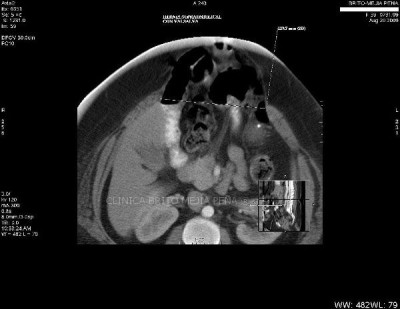

Hernia pared abdominal